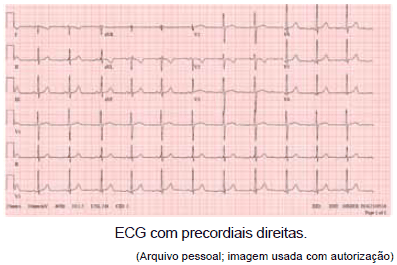

Paciente de 16 anos foi encaminhada ao Pronto-Socorro com quadro de dor torácica, palpitações e palidez cutânea associadas. Ao exame físico, notou-se semiologia cardiovascular normal, porém com ausculta das bulhas em hemitórax direito. Foram solicitados os seguintes exames:

O diagnóstico mais provável é:

Observe as seguintes figuras.

Elas são compatíveis com qual diagnóstico?